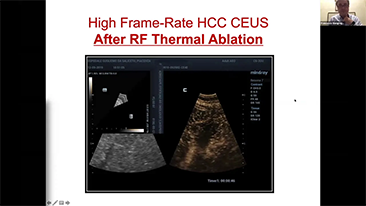

Inzichten

De medische omgeving van vandaag is complexer geworden, met een toenemend aantal moeilijke gevallen en meer werkdruk.